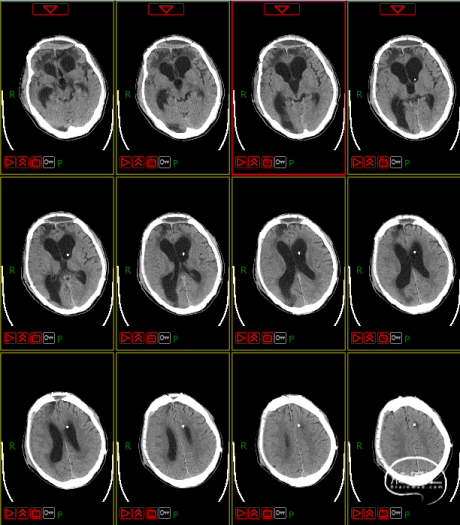

病史及症状描述:主诉:重型颅脑外伤术后意识障碍50天(7月30日入院);现病史:患者2023年6月11日因高处坠落伤在外地行开颅手术等治疗,病情平稳后带气管套管转回湘潭市中心医院(后续简称“我院”)治疗。

入院查体:GCS=E2VTM2=4T分,右侧瞳孔直径约4mm,对光反射迟钝,左侧瞳孔约3mm,对光放射灵敏,四肢关节被动屈伸活动无受限,四肢肌张力偏高,肌力查体无法配合,病理征未引出。

入院诊断:1. 右侧额颞部硬膜下血肿清除术后;2. 颅骨后天性缺损;3. 脑内多发软化灶形成;4. 脑积水;5. 左额骨凹陷性骨折;6. 颅底骨折;7. 左股骨干骨折内固定术后;8. 坠积性肺炎、胸腔积液;9. 气管切开术后;10. 右眼挫伤;11. 下肢肌间静脉血栓;12. 低蛋白血症。

4. 动态复查头部CT

8月21日复查CT:硬膜下积液增加,脑室扩张明显,间质性水肿加重;对患者治疗方案进行调整,转神经外科治疗。